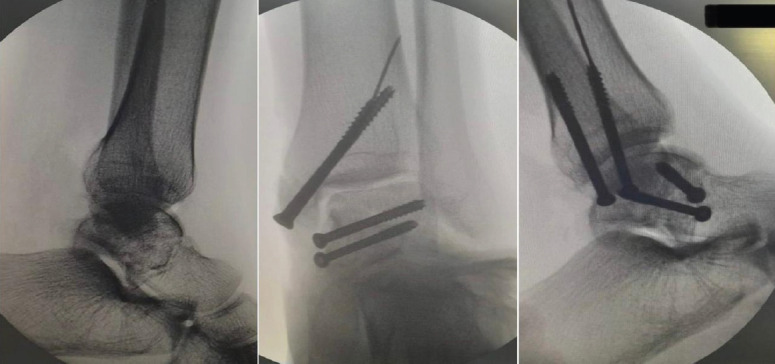

Case report: We share this unusual case of a Hawkins type-3 talus neck fracture along with a serious Grade 3B medial malleolus fracture and ankle subluxation, which was treated with cleaning the wound, realigning the ankle, and surgery to fix the bones. Post-operatively, the wound was healthy and free of infection. Despite being told to avoid weight-bearing for three months, the patient lost follow-up after a month and started occasional partial weight bearing. During the 10th post-operative week, we found a mild degree of talar neck collapse and Hawkins sign radiologically. The range of motion for the ankle was dorsiflexion of 0-15° and plantar flexion of 0-30°, with minimal swelling and pain on weight bearing.

Conclusion: This case highlights the rarity and complexity of a talar neck fracture with ipsilateral medial malleolar fracture and ankle dislocation. Positive early outcomes were achieved through timely surgery within 10 h, careful soft tissue management, and appropriate fixation. The presence of a partial Hawkins sign post-operatively indicated preserved talar vascularity and reduced risk of avascular necrosis.